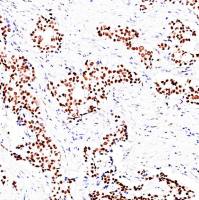

产品名称:MSH2抗体试剂(免疫组织化学)

应用:MSH2是人类错配修复基因家族中一个重要的基因,人类错配修复基因对保持遗传信息的完整性、稳定性及避免遗传突变的产生具有重要作用。突变后该基因缺失,会使细胞错配修复功能缺陷,导致微卫星不稳定(MSI),使肿瘤易感。h MSH2和h MSH6组成的复合体主要识别单个碱基的错配突变和短缺失或插入突变。目前,多和MLH1、MSH6、PMS2共同用于Lynch syndrome的筛查。

阳性部位:细胞核

阳性对照:扁桃体/结直肠癌